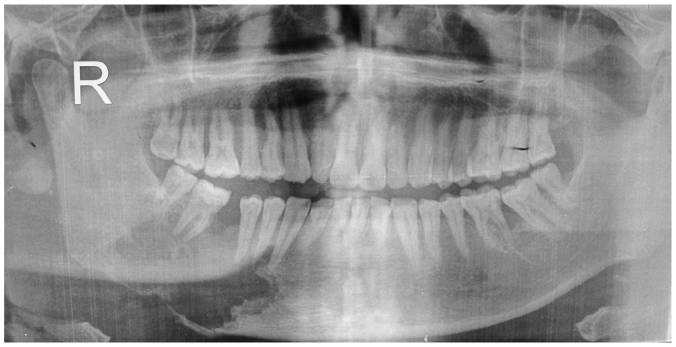

I have what’s called a pathological fracture of the jaw. See the dark gap to the left below the teeth in the image above? Mine’s not that bad fortunately, but it gives you an idea of what’s going on in my mouth. This kind of thing often happens over time to head and neck cancer patients whose treatment protocol included radiation to the tumor bed and surrounding area. The advanced stage of my tongue cancer in 2005 required no less than thirty-nine such blasts. Allow me to quote one doctor who examined me after this morning’s dive. “There is so much damage down there.” To use my own words, my mandible is a shambles. No way it heals on its own, regardless of the number of dives I execute or any other healing strategy doctors might bring to bear on it. This man’s jaw, at least the right lower side, can no longer fight the good fight.